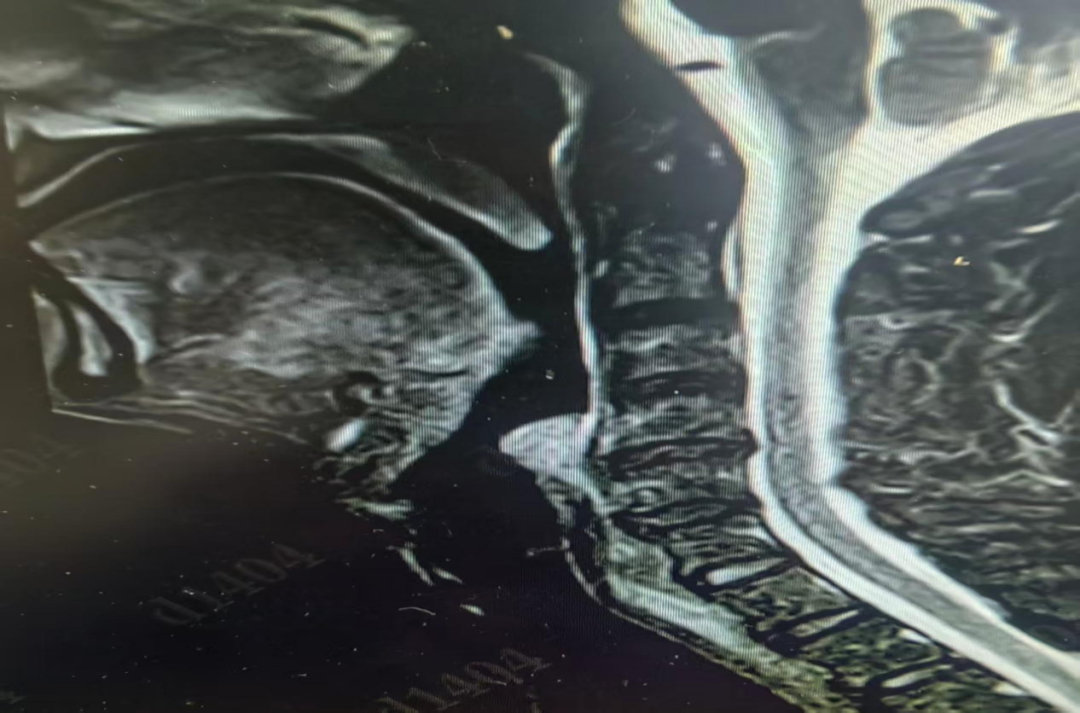

患者通过“一站式住院”快捷办理入院,住院医师刘璇与上级医师黄准迅速为李伯伯安排了喉部核磁共振增强检查。结果指向了一个罕见的诊断:左梨状窝血管瘤。

图片